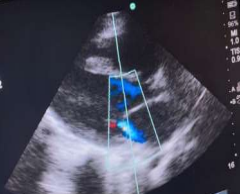

Initial complete blood count showed moderate normochromic and macrocytic anemia (hemoglobin: 8.9 mg/dL, MCV: 91.6 fL, MCHC: 32.6 g/dL), leukocytosis (white blood cells: 18,800/mm3), lymphopenia (lymphocyte count: 11.5% with an absolute lymphocyte count [ALC] of 2,162 cells/mm3), elevated inflammatory markers (CRP: 96 mg/L, ESR: 80 mm/h), elevated creatinine (0.93 mg/dL), abnormal coagulation parameters (D-dimer: 1,947 ng/mL, INR: 4.07, PT: 38.3 s), and abnormal liver function tests (total bilirubin: 0.42 mg/dL, AST/GOT: 50 U/L, ALT/GPT: 107 U/L). The post-COVID-19 Multisystem Inflammatory Syndrome diagnosis was made, even though COVID-19 PCR and serology results for IgM were negative, as IgG was positive. Other tests, including troponin I, COVID-19 antigen, and rapid malaria test, were also negative. Urine and blood cultures were sterile. She underwent two echocardiograms: the first one before her transfer showed mild to moderate mitral regurgitation, right coronary artery dilation at 6 mm, left coronary artery dilation at 5 mm, and a z-score of 5 (Images 3 and 4). The second echocardiogram, performed one week later, indicated probable post-infectious myopericarditis. Chest radiography revealed infiltrates.

Image 3: mitral regurgitation

Image 4: right coronary artery dilation at 6 mm, left coronary artery dilation at 5 mm, and a z-score of 5